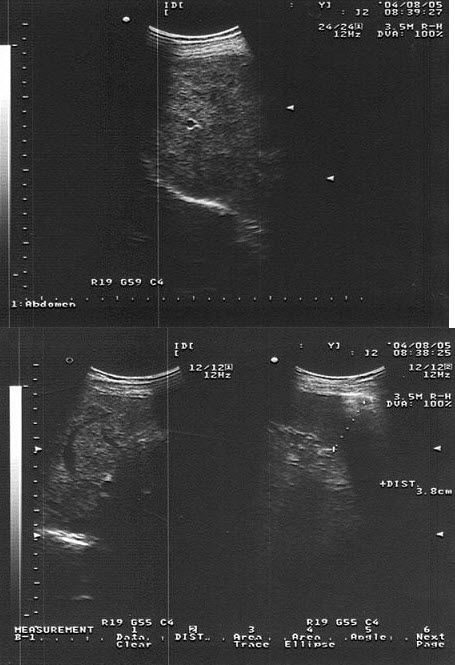

患者,女性,转移性右下腹疼痛4小时,超声见一长条低回光团,边界不清,如图所示,考虑为()

A.肝管结石

B.胆囊炎

C.附件炎

D.阑尾炎

E.肠梗阻